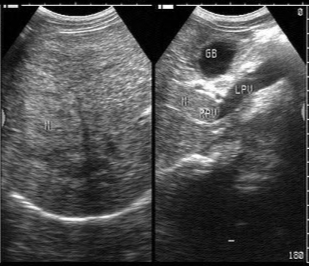

(7)符合影响诊断学。如超声显示:肝区近场弥漫性点状高回声(肝区回声密集增强),远场(或后方)回声衰减。

(4)其首选检查是超声,其超声表现和非酒精性肝病极其相似。确诊的方法用肝穿刺活组织检查。